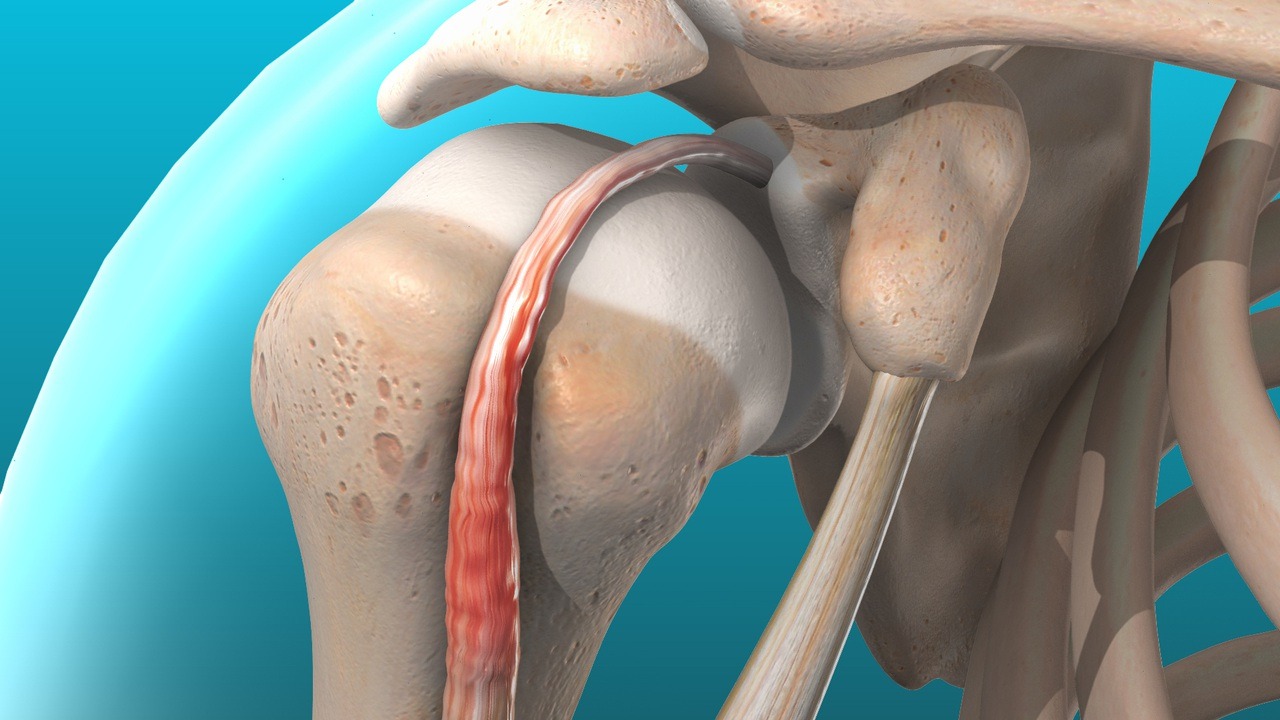

تزریق پلاسمای غنی از پلاکت (PRP)

این روش برای تحریک روند ترمیم طبیعی تاندون و کاهش درد کاربرد دارد و در بیماران مزمن که به درمان های سنتی پاسخ نمی دهند، موثر است.

در این روش، پارگی تاندون ترمیم می شود و ساختار طبیعی مفصل بازسازی می گردد.

جراحی آرتروسکوپی

با استفاده از ابزارهای کم تهاجمی، پزشک می تواند تاندون آسیب دیده را ترمیم کرده و بافت های ملتهب را پاکسازی کند. این روش باعث کاهش دوره نقاهت و بازگشت سریع تر به فعالیت می شود.